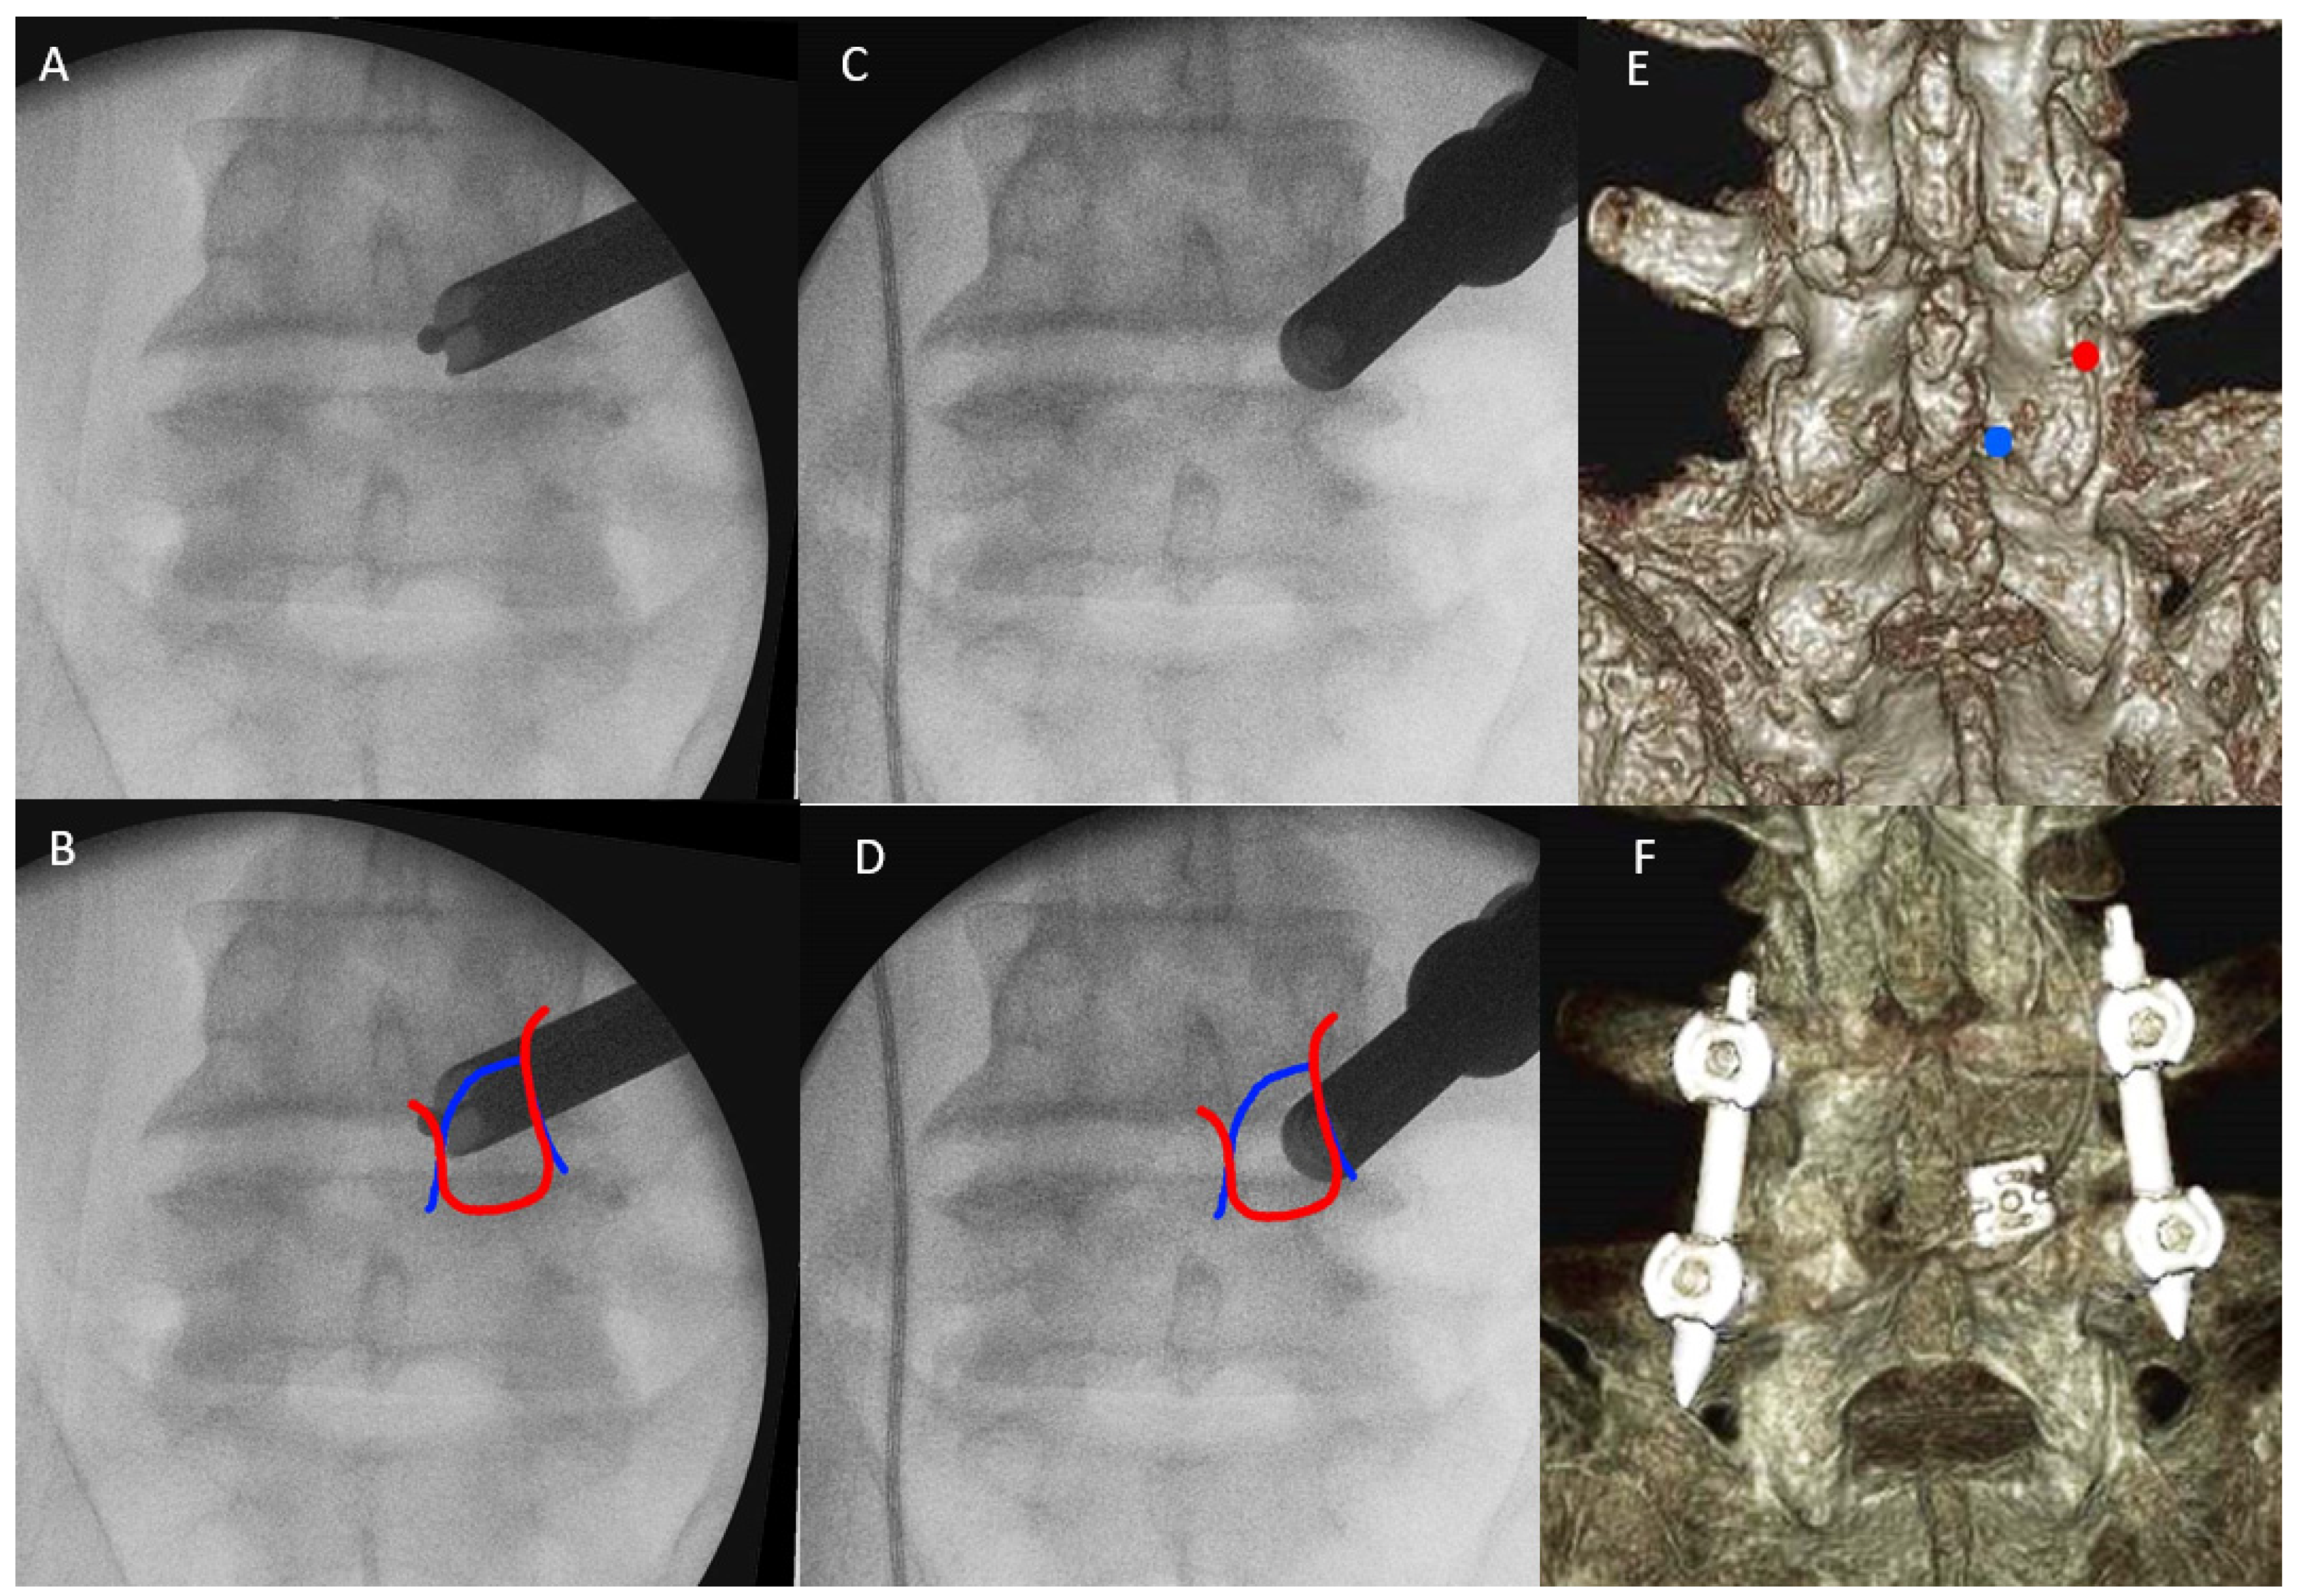

2.4.1. Docking of Endoscope on Isthmus

2.4.2. Handling of Inferior Articular Process: ETLIF (I) versus ETLIF (O)